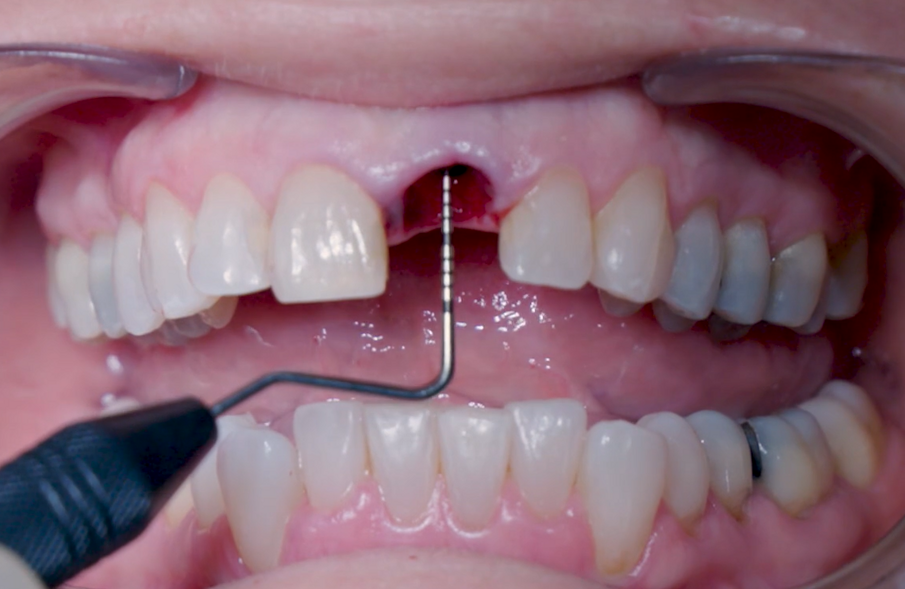

La fresa preliminare da Ø 2,2 mm è stata utilizzata sulla rispettiva lunghezza prevista dall’impianto, seguita da un perno di allineamento per controllare l’orientamento in 3D (Figg. 6, 7). Le frese da Ø 2,8 mm e Ø 3,2 mm sono state utilizzate per completare l’osteotomia (Fig. 8). Il sito è stato quindi opportunamente sondato per valutare la possibile perforazione della parete. Un impianto 4×14 mm è stato posizionato, a partire dalla maniglia chirurgica che coinvolge la parte apicale dell’impianto, seguendo lo stesso orientamento dell’ago perforatore e correggendo la direzione dell’impianto mentre si spostava all’interno dell’osteotomia (Figg. 9, 10). La stabilità primaria (45 Ncm) è stata raggiunta nella posizione finale.

Fig. 11_Valutazione finale della posizione dell'impianto.

Fig. 12_Valutazione finale della posizione dell'impianto in relazione ai margini gengivali.